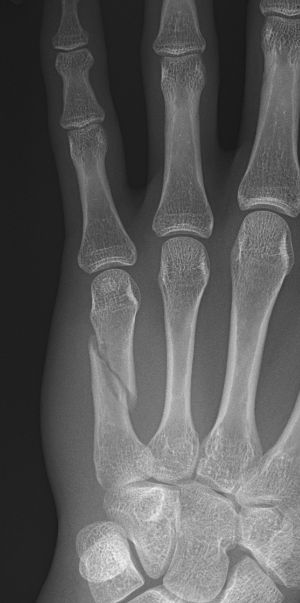

Bennett-fraktur = Green I: intraartikulär luxationsfraktur genom basen av metakarpale 1, volart-ulnart fragment ligger på plats medan APL-senan drar distala fragmentet radialt-proxmalt.

Rolando-fraktur = Green II: intraartikulär komminut fraktur genom basen av metakarpale 1, ofta Y- eller T-formad.

Transversell extraartikulär fraktur = Green IIIa.

Sned extraartikulär fraktur = Green IIIb.

Tenneb-fraktur = omvänd bennettfraktur: intraartikulär fraktur i basen av metakarpale 5, volart-radialt fragment ligger på plats medan ECU-senan (extensor carpi ulnaris) drar distala fragmentet ulnart-proximalt.